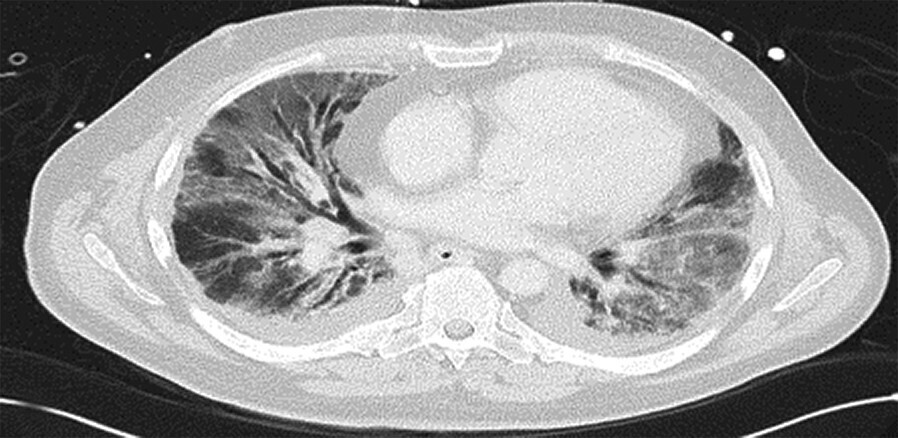

- Radiomorphologisch findet man bei einer akuten Exazerbation einer bestehenden Lungenfibrose Milchglasverschattungen, teilweise auch Konsolidierungen auf dem Boden fibrotischer Veränderungen (Abb. 36.3a). Bei einer akuten interstitiellen Pneumonie (AIP), die sich klinisch ähnlich äußert, fehlen die fibrosierenden Veränderungen (Abb. 36.3b).

Abb. 36.3 Radiologie bei akuter Exazerbation einer idiopathischen Lungenfibrose (IPF) und akuter interstitieller Pneumonie (AIP).

In beiden Fällen sieht man ausgedehntes Milchglas, jedoch nur bei der IPF auch das „UIP-Muster “mit den Honigwaben und Traktionsbronchiektasen).

a HRCT eines Patienten mit akuter Exazerbation einer IPF. (Quelle: Prof. Heußel und Prof. Kreuter, Thoraxklinik Heidelberg)

b HRCT eines Patienten mit AIP. (Quelle: Prof. Heußel und Prof. Kreuter, Thoraxklinik Heidelberg)